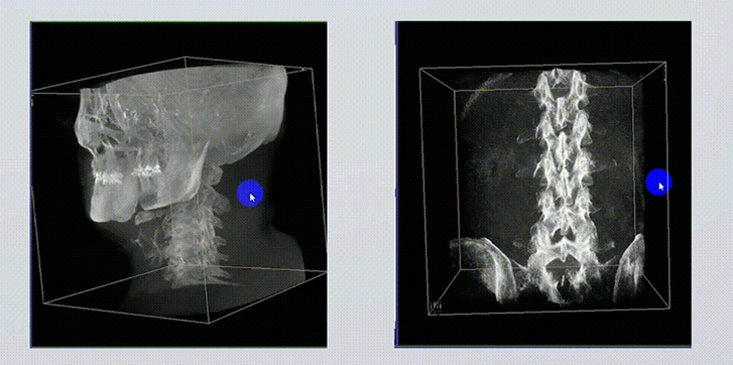

1、術(shù)中實(shí)時(shí)三維成像

術(shù)中三維成像和橫斷面圖像提供多角度的手術(shù)診斷信息,輔助醫(yī)生進(jìn)行術(shù)中評(píng)估判斷,諸如骨折復(fù)位情況和內(nèi)植入螺釘?shù)某叽绾臀恢?,輔助手術(shù)更好地完成。

提供更大的術(shù)中三維成像視野,采集更多圖像信息,可一次拍全全段頸椎、全段腰椎、七節(jié)胸椎、雙側(cè)骶髂關(guān)節(jié)、股骨頭及單側(cè)盆骨。